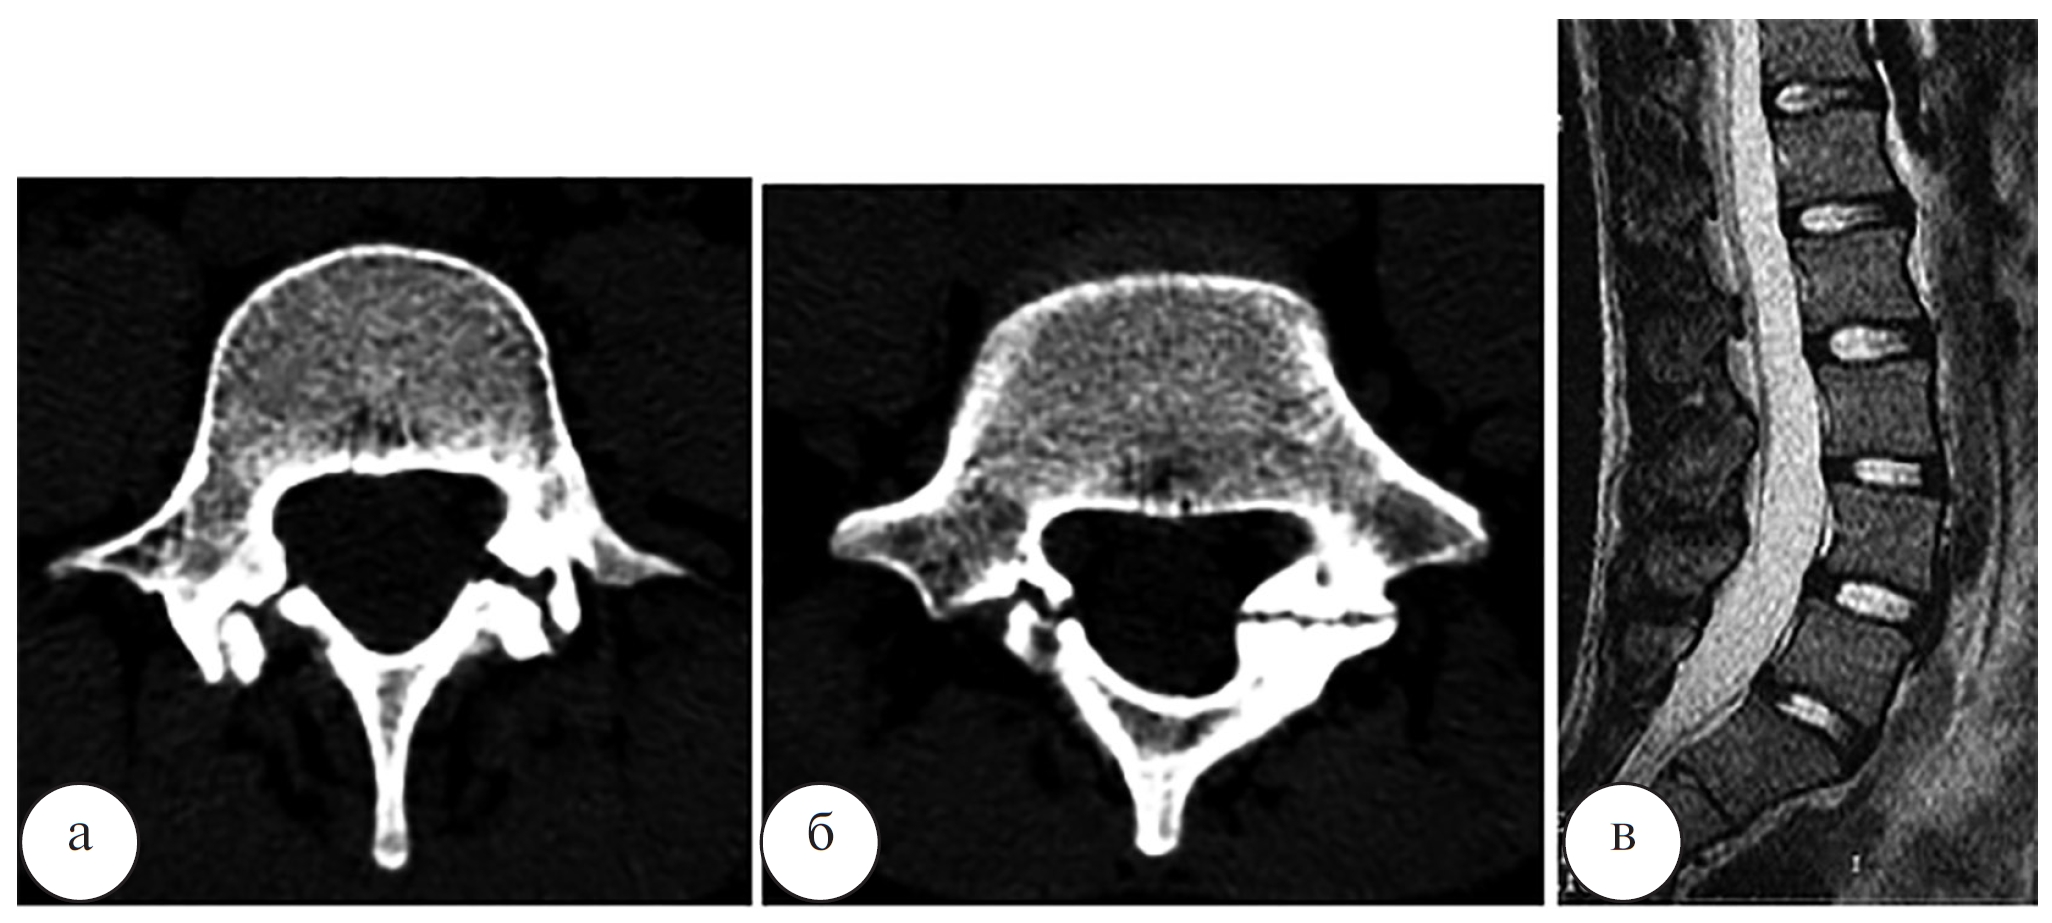

Рис. 2. Рентгенограмма (а) и МР-томограмма (б) поясничного отдела позвоночника в боковой проекции, компьютерная томограмма L5 позвонка в аксиальной проекции (в) пациента О. до операции

Наблюдение 1. Пациент О., 19 лет, профессиональный спортсмен. Диагноз: двухсторонний спондилолиз L5 позвонка с болевым синдромом. Рентгенограммы, МРТ и КТ пациента О. до операции, сразу после операции и через 4 месяца после операции представлены на рисунках 2–4.